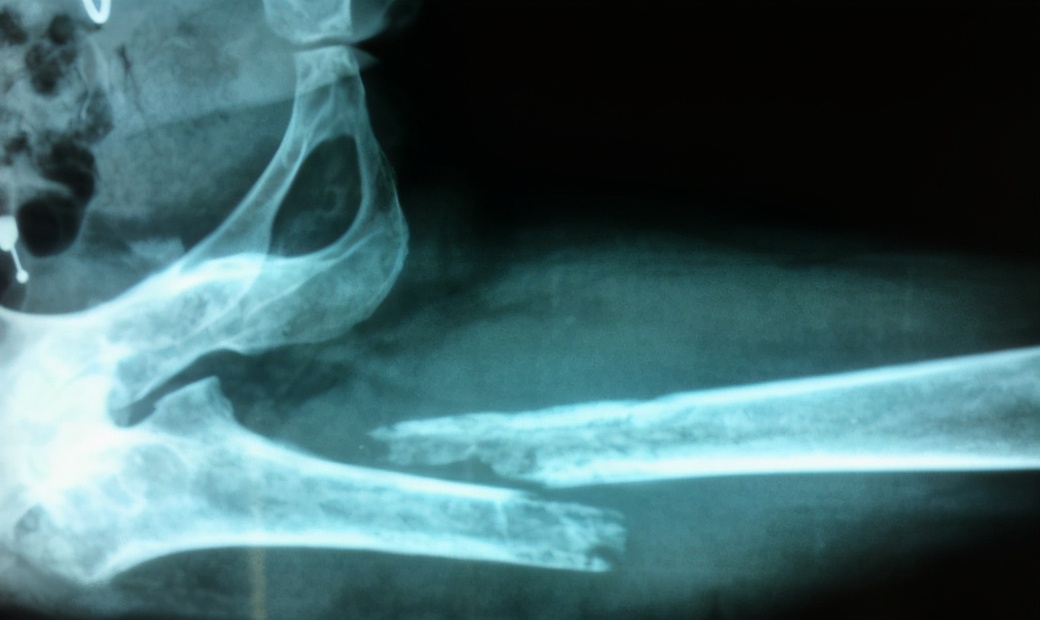

第一种情况是出现病理性骨折:骨髓炎到慢性发展阶段时,在骨的破坏比较严重时,骨包壳尚未形成之前,也就是在骨包壳并不牢固的时候,容易导致病理性骨折。这时候,我们需要对患肢进行保护,一般我们要采取石膏进行固定或是进行牵引治疗,这样才能够有效的预防病理性骨折的发生。